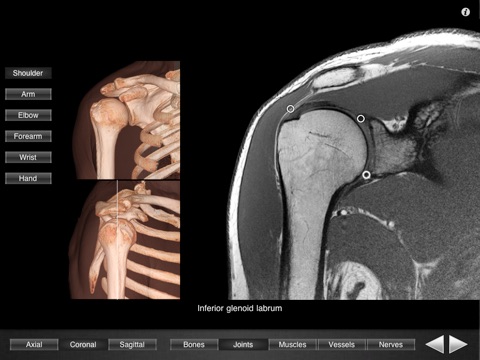

Monster Anatomy - Upper Limb is an interactive lower limb radiology atlas developed in the Medical Imaging Department of the University Hospital Center of Nancy, France, under the supervision of Professor Alain Blum.

Monster Anatomy – Upper Limb is the complement of Monster Anatomy HD – Lower Limb and is compatible with iPhone and iPad. This application is designed for healthcare professionals (Radiologists, General Practitioners, Orthopedists, Surgeons, Physiotherapists among others) as well for students, as a reference and learning tool. It contains 502 contiguous MR slices (2-4 mm thickness) in the three anatomical planes.

- 3D Image volume (VR) allows precise location of slice position.

- The five different display modes available (bones, joints, muscles, blood vessels and nerves) facilitates label visualization. - High image quality with a zooming tool.